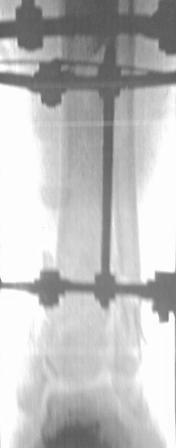

[Ortho] Открытый перелом 43.С3.3

Больной 41г переведен из ЦРБ, травма в  результате ДТП- 5 дней

назад, произведена ПХО  раны, наложена  гипсовая  повязка.

Об-но; начиная  с  с/з  голени  продольно - почти циркулярная рана, с

признаками инфицирования - покраснение, отечность, усиление  боли,

местная  т-ра и  мутные  кровянистые выделения из  раны, и

выраженная деформация голени. В отд нашей коллегой в  экстренном

порядке в  задней  поверхности голени щвы  распушены, выпушено около

50мл мутная  гематома, АВФ, умеренная дистракция, антибиотики, и т.д.

Наш план; после устранения воспалительных процессов, перемонтаж

аппарата, репозиция оставшихся смешений спицами с  упорной

плошадкой и  стабилизация аппарата, дальше  по  обстановке.